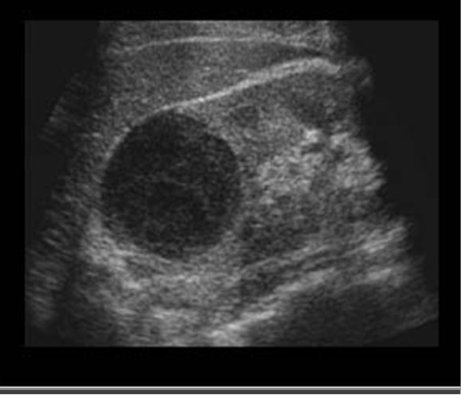

Echogenicity

Level of gray or brightness on an ultrasound image

Described in relation to surrounding tissues

Isoechoic

Uniform in color

Liver

Hypoechoic

abscesses, fatty tissue

Darker = less echoes

Hyperechoic

Bone, kidney/gallbladder stone

lighter = more echoes

Anechoic

no echos

Bladder, cystic fluid, gallbladder

Artifacts-enhancement

Acoustic enhancement- sound travels through fluid uninterrupted, so the echoes deep to a fluid collection are brighter than the adjacent tissue

In poorly attenuating objects such as a cyst, the echoes returning from regions deep to the object are of higher amplitude

Artifacts- shadowing

A structure that blocks the sound wave causes acoustic shadowing (gallstones)

Strongly attenuating or highly reflective surface, the returning echoes posterior to the structure are decreased in amplitude